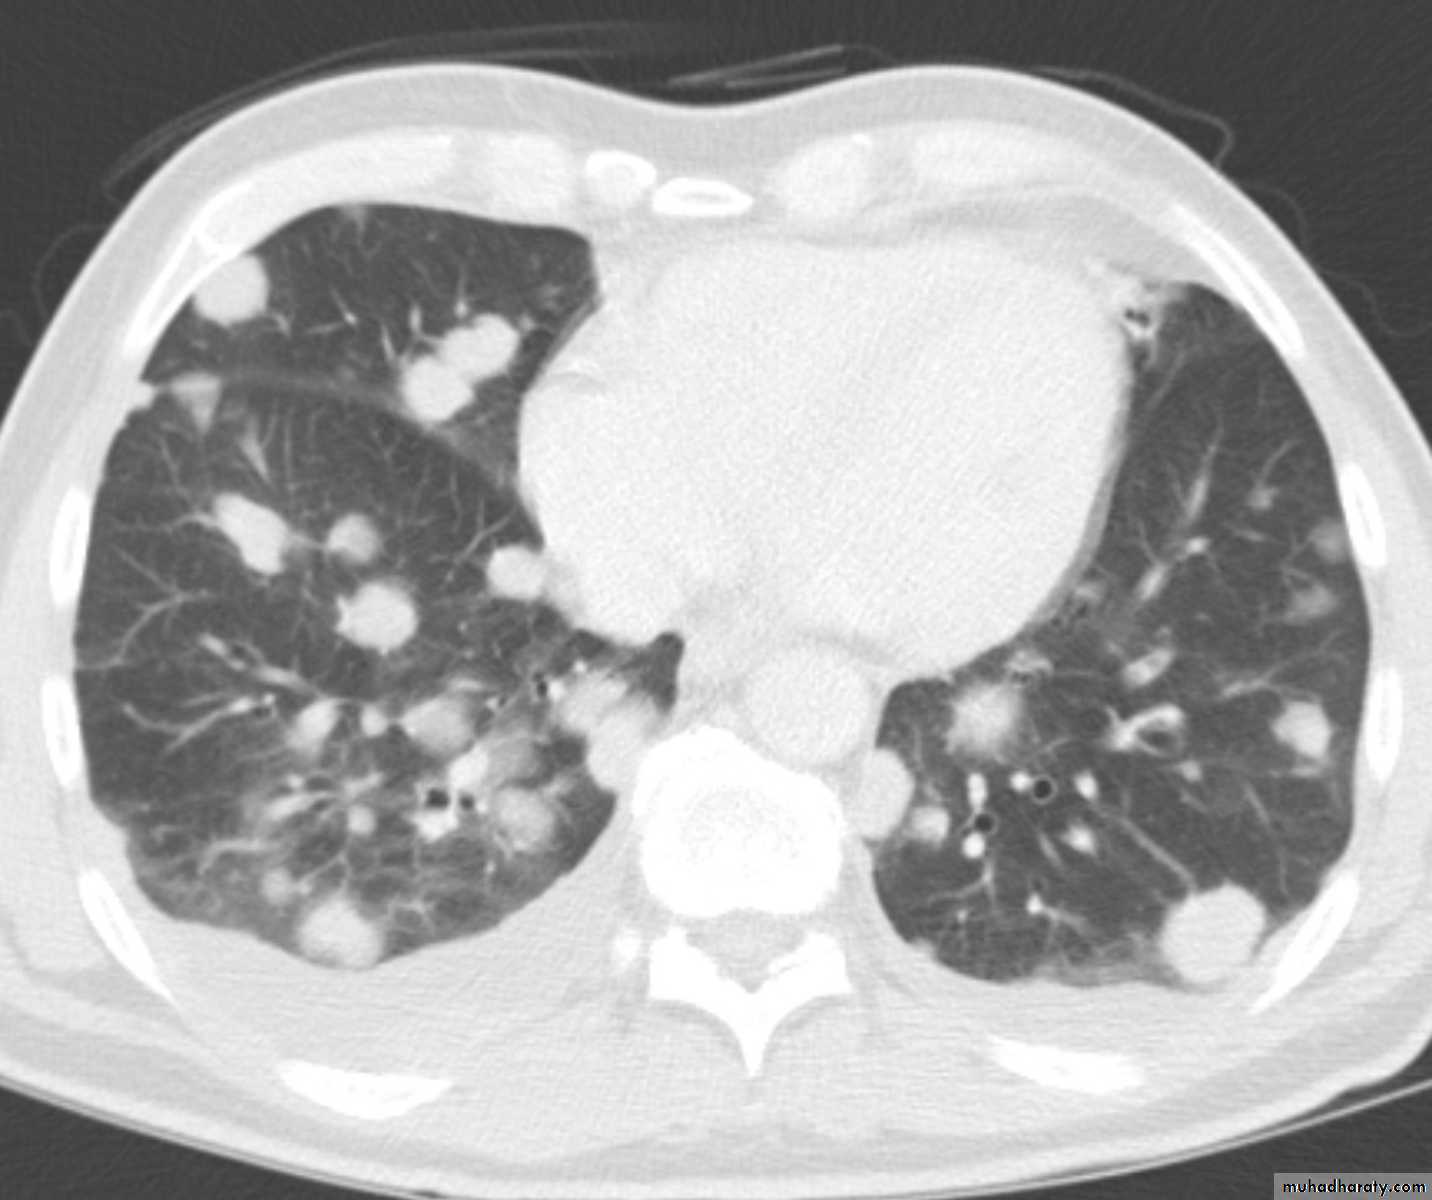

Chest CT scan shows multiple round nodules and masses of varying sizes in both lungs, consistent with metastases. There are also small bilateral pleural effusions.